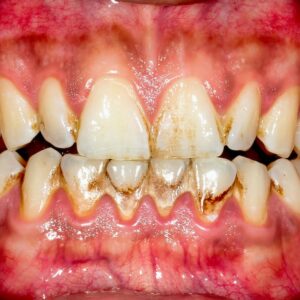

Impact on Gum Health

Another effect of caffeine is its tendency to cause dry mouth. Coffee reduces saliva production, and since saliva is the mouth’s natural defense system, a lack of it can allow bacteria to thrive. This environment can irritate gums, contribute to plaque buildup, and eventually increase the risk of gum disease.

- Plaque buildup – A rough texture or dull appearance on teeth.

- Gum irritation – Swelling, redness, or tenderness.